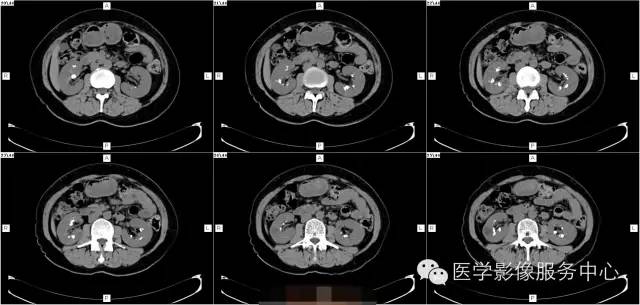

病史:

女,37岁,血尿一周

髓质海绵肾(简称MSK)又称Cacchi Ricci disease,是一种先天发育性肾髓质囊性病变,发生率约1:2000-5000,多见于40-60岁男年,70%为双侧肾脏发病,病变局限于髓质范围内,常累及两侧肾的多数锥体和乳头,形成许多数毫米的囊腔使髓质如海绵状,故名海绵肾,病理特点为集合管远端扩张,形成圆形或不规则型囊腔,囊内壁衬以立方或扁平上皮,囊内充溢脱离的上皮及钙化形成的小结石。

3、CT平扫表现一个或多个肾锥体内散在或蔟团状多发结石,呈花瓣样或扇形分布;部分腹部平片阴性,CT平扫可发现肾锥体内细小的结石。增强扫描表现扩张的肾集合管内有条纹状、刷状、小囊状或扇形的造影剂浓聚。部分患者肾实质内可见多发小囊肿。

1、肾钙盐沉积 :为肾集合管内及其周围弥漫性钙盐沉积,病变广泛,但不伴有集合管扩张,常见于肾小管酸中毒、甲旁亢、特发性高尿酸钙等

2、肾结核 病变不局限于肾乳头部,累及范围广,病灶不规则, IVP检查可显示肾盏虫噬样改变。

3、肾盏内散在小结石与不典型髓质海绵肾鉴别 海绵肾小结石位于肾乳头内,很少大于5mm,位置固定 ,IVP检查可见集合管囊状扩张,B超、CT检查可进一步明确诊断。

4、肾乳头坏死形成的钙化 病变位于肾盏顶部或锥体的尖端,钙化呈环状或三角形,密度均匀,病变中心因乳头坏死呈空腔改变,可伴肾盏变形和肾功能损害。